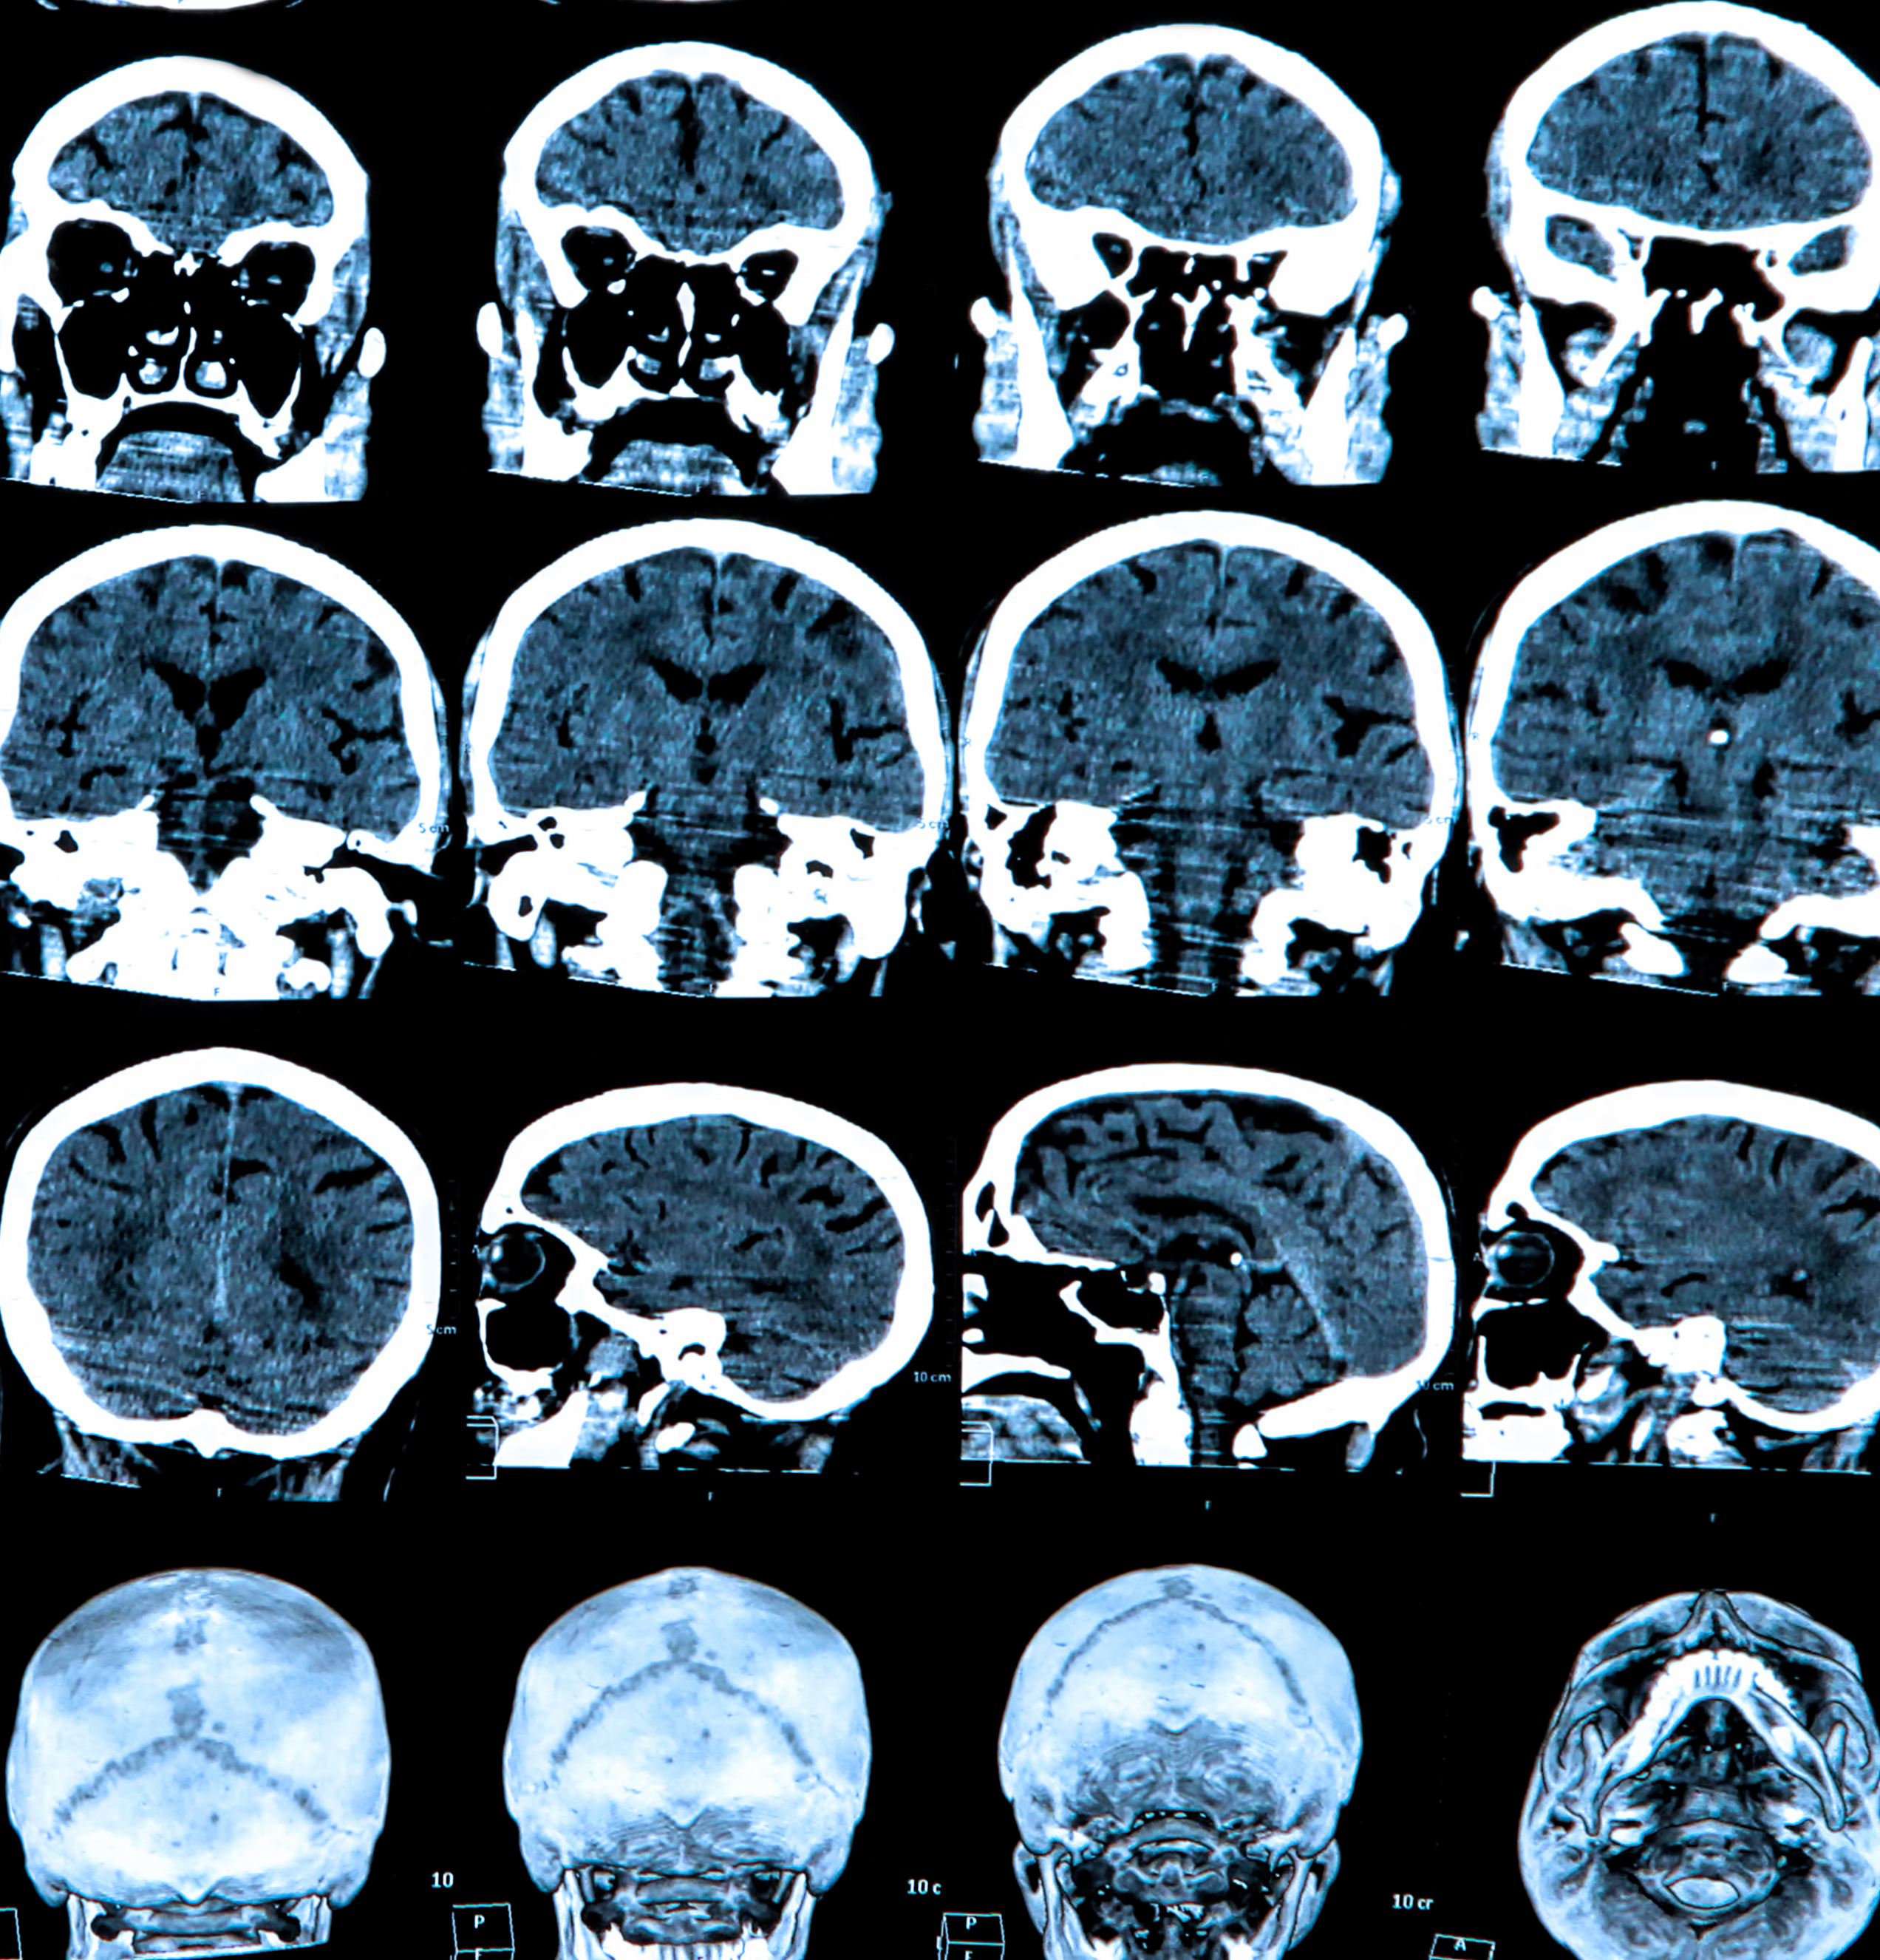

DaT scan is a single photon emission computer tomography (SPECT) nuclear imaging technique which uses a 123Iodine (123I)- labelled ligand bound to the dopamine transporter (DaT) to visualize functioning at the presynaptic dopaminergic neural terminal. A reduced DaT signal reflects presynaptic functional dopaminergic neuron loss.

“Usually what you see in PD is asymmetric signal loss starting from the posterior putamen to the caudate nucleus. But be careful, abnormal imaging doesn’t equate with PD. It could be PSP, MSA or PD,” Dr Tao reported.